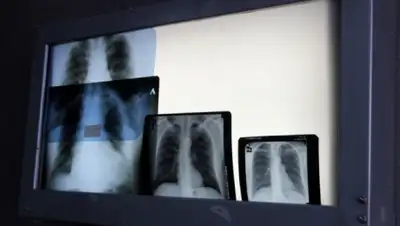

- Пробу Манту не делали, - сообщили в ведомстве. - Родители девочки сами обратились в поликлинику, когда она вдруг начала чувствовать себя плохо, появились кашель и температура. Сначала ей назначили обычное лечение от простуды. Однако улучшений не последовало, и ей сделали рентгенографию, по результатам которой появилось подозрение на пневмонию. После этого пациентку перевели в Центр матери и ребенка и сделали повторную рентгенографию. Она-то и показала, что у школьницы инфильтративный туберкулез левого легкого. Девочку госпитализировали в детский противотуберкулезный диспансер в Семее. Она в 2011 году уже перенесла это опасное заболевание, в течение года лечилась и, полностью восстановившись, была снята с учета и допущена к занятиям.

По словам специалистов, тяжелый недуг приняли за пневмонию, так как первоначальные снимки не показали заразного заболевания легких. В медицинском ведомстве также добавили, что уже составлен список лиц, которые могли контактировать с девочкой в стенах школы и за ее пределами. Все они начали проходить обследование. Пока не ясно, успел ли кто-нибудь подхватить опасную инфекцию.